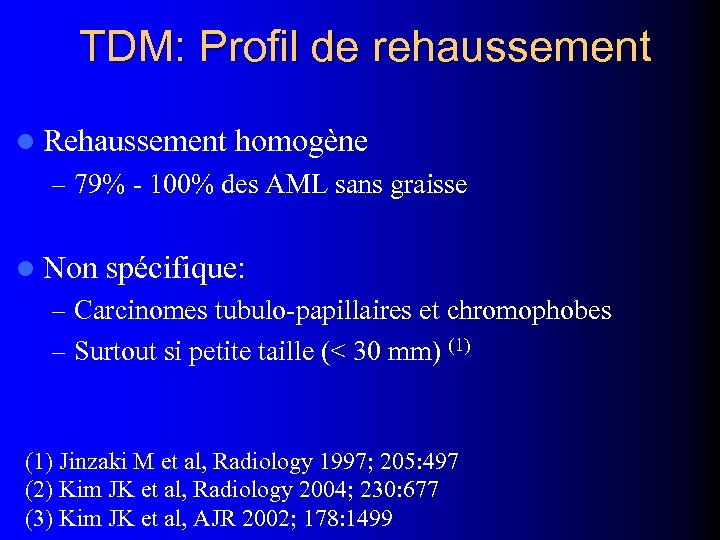

TDM: Profil de rehaussement l Rehaussement homogène – 79% - 100% des AML sans graisse l Non spécifique: – Carcinomes tubulo-papillaires et chromophobes – Surtout si petite taille (< 30 mm) (1) Jinzaki M et al, Radiology 1997; 205: 497 (2) Kim JK et al, Radiology 2004; 230: 677 (3) Kim JK et al, AJR 2002; 178: 1499

TDM: Profil de rehaussement l Rehaussement homogène – 79% - 100% des AML sans graisse l Non spécifique: – Carcinomes tubulo-papillaires et chromophobes – Surtout si petite taille (< 30 mm) (1) Jinzaki M et al, Radiology 1997; 205: 497 (2) Kim JK et al, Radiology 2004; 230: 677 (3) Kim JK et al, AJR 2002; 178: 1499